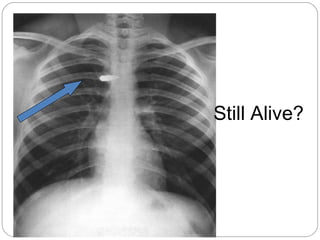

Still Alive?

…That was

close

Bullet can be in

any of these places

(anterior to

posterior at same

level)

1 - spinal cord

2 - trachea

3 – Superior

Vena Cava

4 - aorta